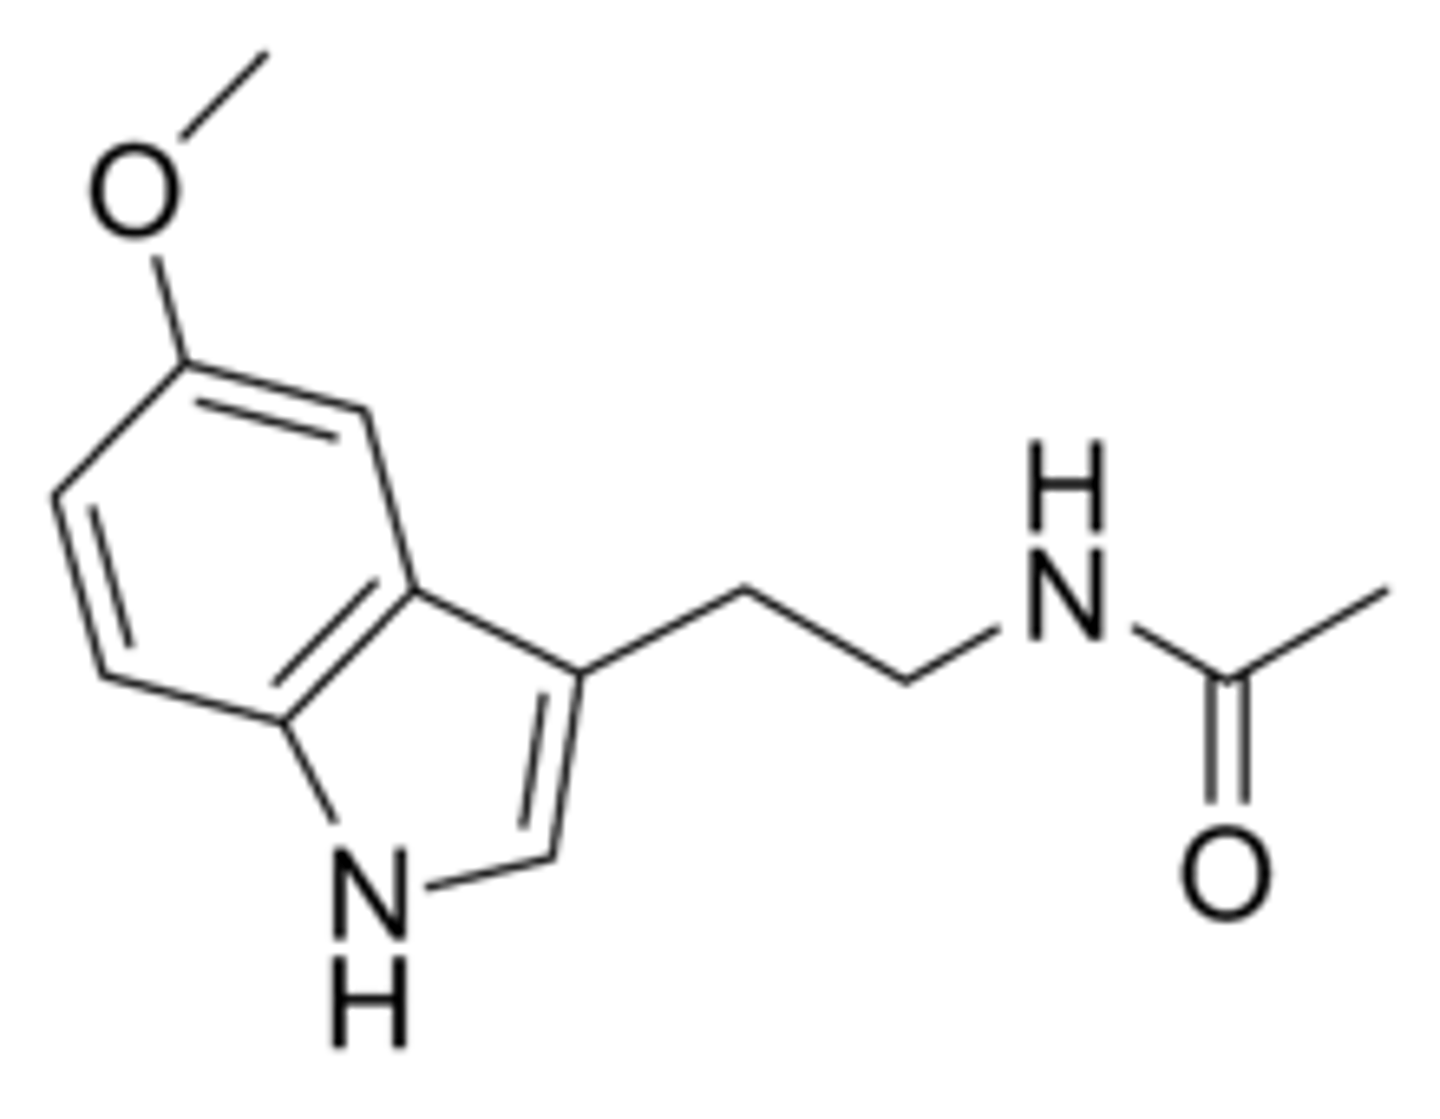

Melatonin

a hormone manufactured by the pineal gland that produces sleepiness.

Serotonin

a neurotransmitter related to things such as mood, sleep, temperature regulation, memory, pain, and sexual activity